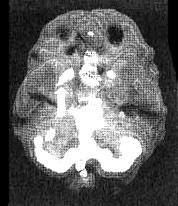

Мозг Билла — мозг влюбленного человека

Иллюстрация к книге — Измените свой мозг - изменится и жизнь! [i_038.jpg]

Трехмерное изображение — активный мозг, вид снизу. Обратите внимание на повышенную активность базальных ганглиев слева и справа (помечено стрелками).